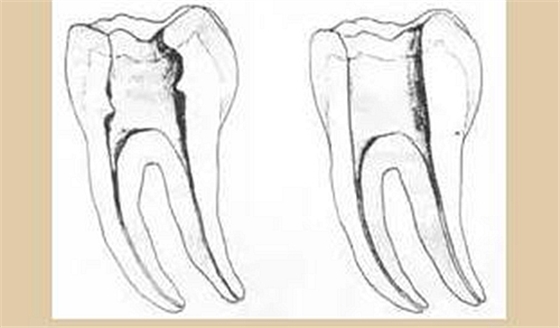

三、開(kāi)髓孔

1. 正常開(kāi)髓孔的位置和大小

左圖為正常開(kāi)髓孔的大小和位置。左邊圖為下顎,右邊圖為上顎。

2. 根管治療中開(kāi)髓孔的設(shè)計(jì)標(biāo)準(zhǔn)

根管治療需去除髓腔內(nèi)容物(去除髓室頂),建立所有根管的入路,允許沖洗液大量沖洗。開(kāi)髓孔的設(shè)計(jì)標(biāo)準(zhǔn)以建立通路為目的,從而建立良好的視野和術(shù)野。

( 1 )直線(xiàn)通路:根管治療時(shí)需要一個(gè)直線(xiàn)通路,直線(xiàn)通路能夠達(dá)到根尖三分之一

測(cè)量標(biāo)準(zhǔn):以允許根管器械直線(xiàn)并直接進(jìn)入根尖 1/3 且不接觸冠方各壁為標(biāo)準(zhǔn)。

( 2 )髓腔其他改變:如髓室頂、繼發(fā)性牙本質(zhì)、修復(fù)性或增齡性牙本質(zhì)。見(jiàn)左圖。

右圖中有繼發(fā)性牙本質(zhì),切削后獲得直線(xiàn)通路。